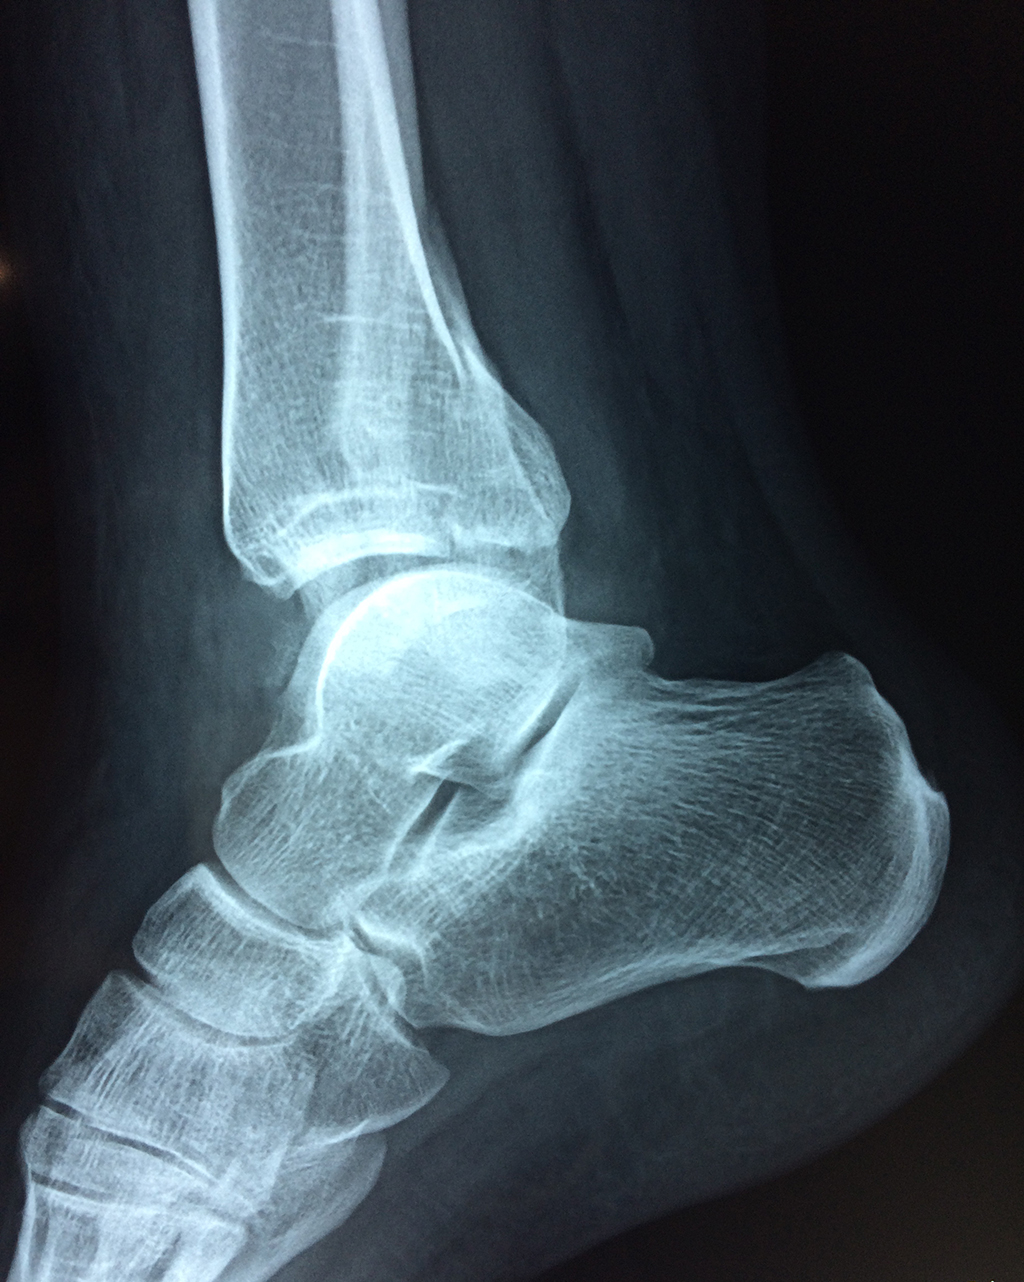

Cirugías de Peroné y Tibia

Una fractura de tobillo es la rotura de uno o más de los huesos del tobillo. Estas fracturas pueden ser:

Algunas fracturas de tobillo pueden requerir cirugía si:

- Los extremos de los huesos están desalineados entre sí (desplazados).

- La fractura se extiende hasta la articulación del tobillo (fractura intra-articular).

Cuando se necesita cirugía, es probable que esta implique el uso de clavijas de metal, tornillos o placas para sostener los huesos en su lugar mientras la fractura se consolida. Los elementos de soporte pueden ser temporales o permanentes.